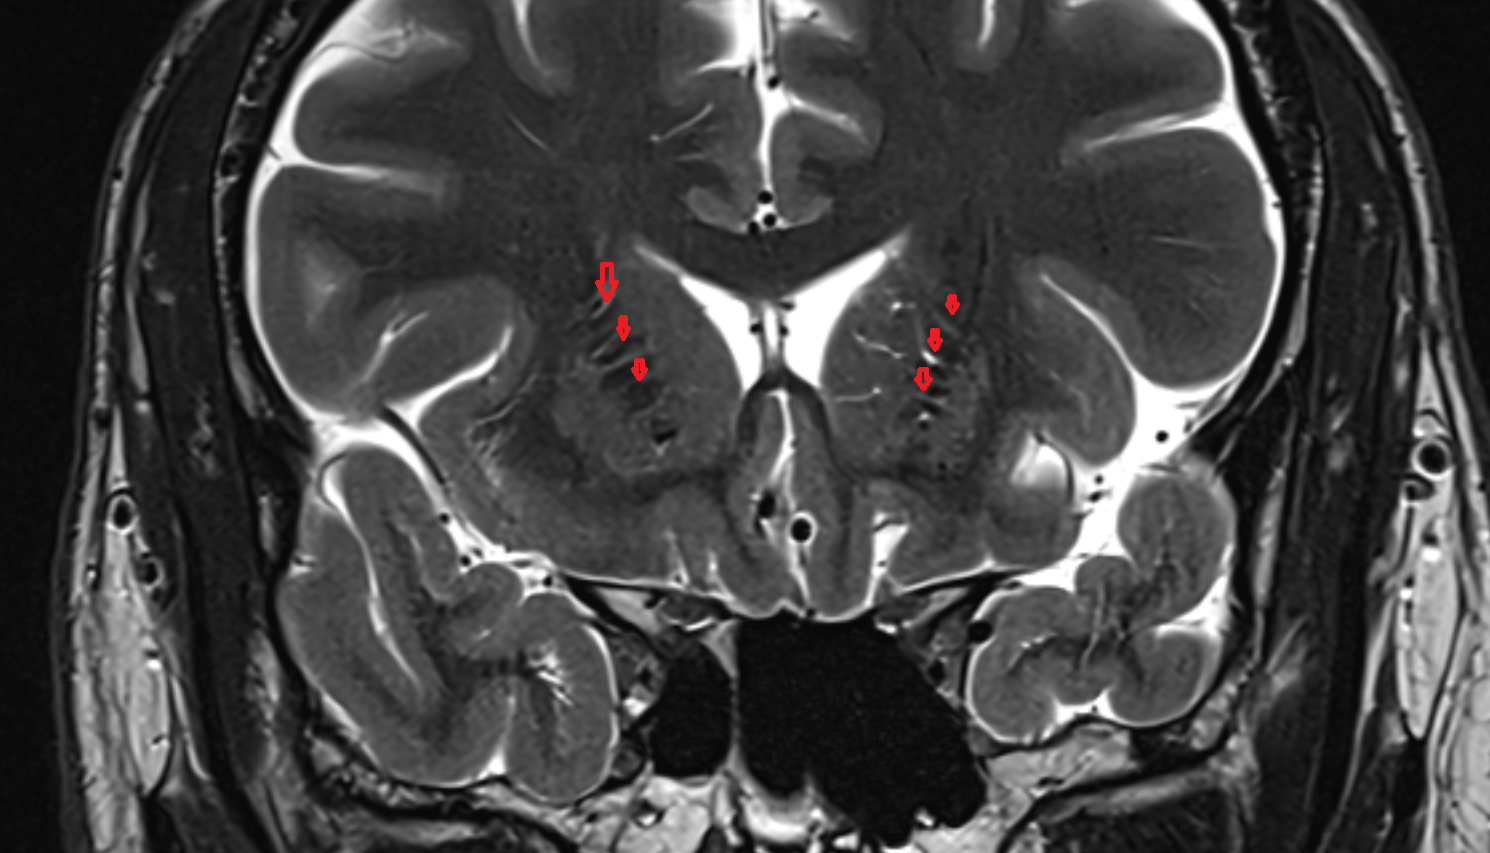

- Hippocampal body

- Hippocampal head

- Hippocampal tail

- Body of hippocampus

- Head of hippocampus

- Tail of hippocampus

- Hippocampus